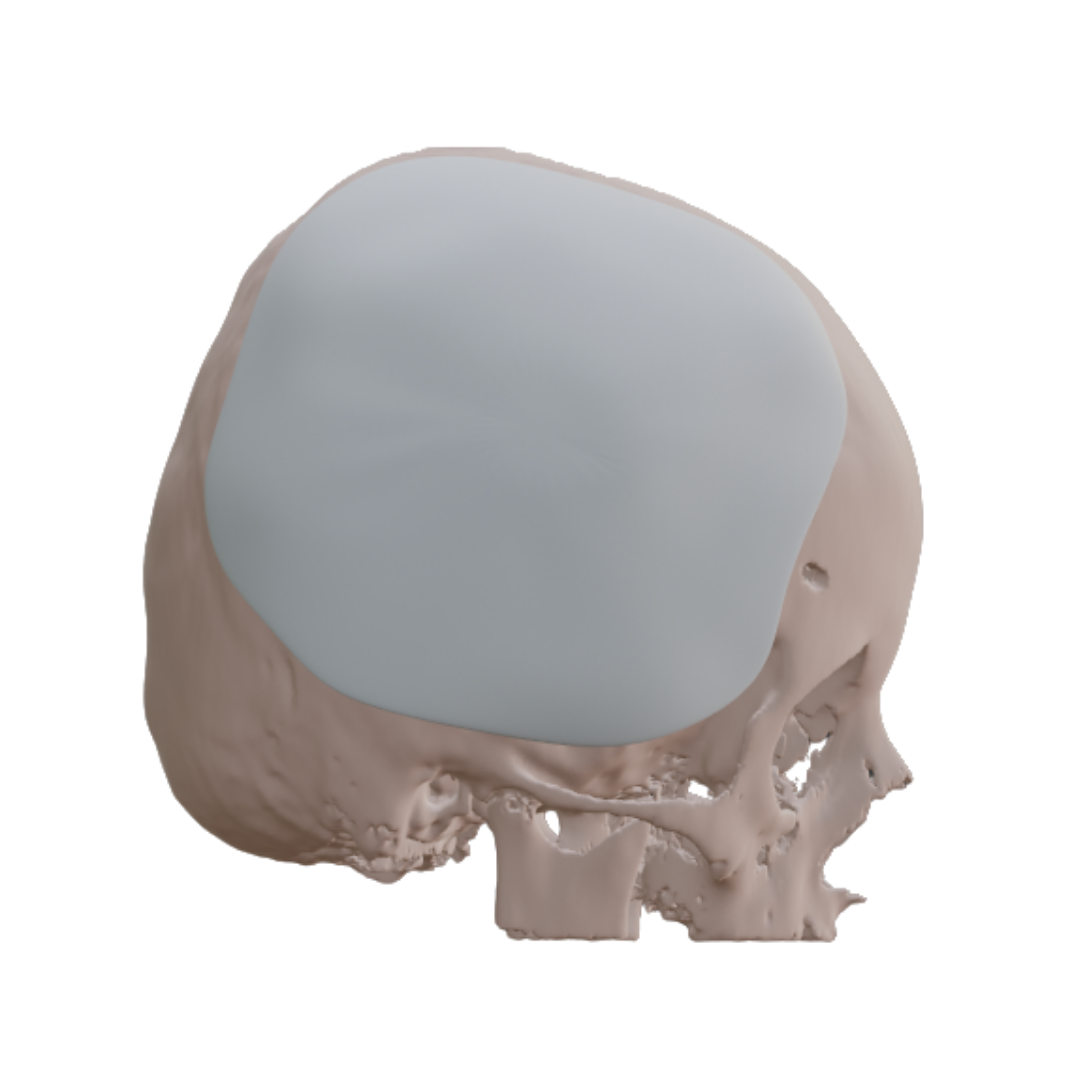

NEURO

We Design Not Only Bone, But Also the Future

Bloocell® is the world’s first “ARTIFICIAL TISSUE TECHNOLOGY” developed in the field of tissue engineering for the treatment of tissue deficiencies. It is a complementary and therapeutic solution that can be manufactured in patient-specific anatomical forms. With its innovative technology, Bloocell® has become the first legal representative of this paradigm worldwide.Clinical results have been consistently successful. Bloocell® is a three-dimensional scaffold designed for the treatment of damaged or missing tissues. It offers a holistic therapeutic approach by supporting cell growth, tissue formation, and the healing process. While reinforcing the tissue structure, Bloocell® also facilitates cell proliferation and differentiation in an optimized environment. Made from biologically compatible materials, Bloocell® does not induce adverse immune responses once integrated into the body. As a bioresorbable scaffold, Bloocell® is gradually absorbed and replaced by new tissue. This process provides an ideal environment for natural tissue regeneration and repair. Bloocell® can reconstruct various tissue types such as bone, cartilage, soft tissue, skin, and nerves. Therefore, Bloocell® offers a broader application range than grafts and carries lower associated risks.